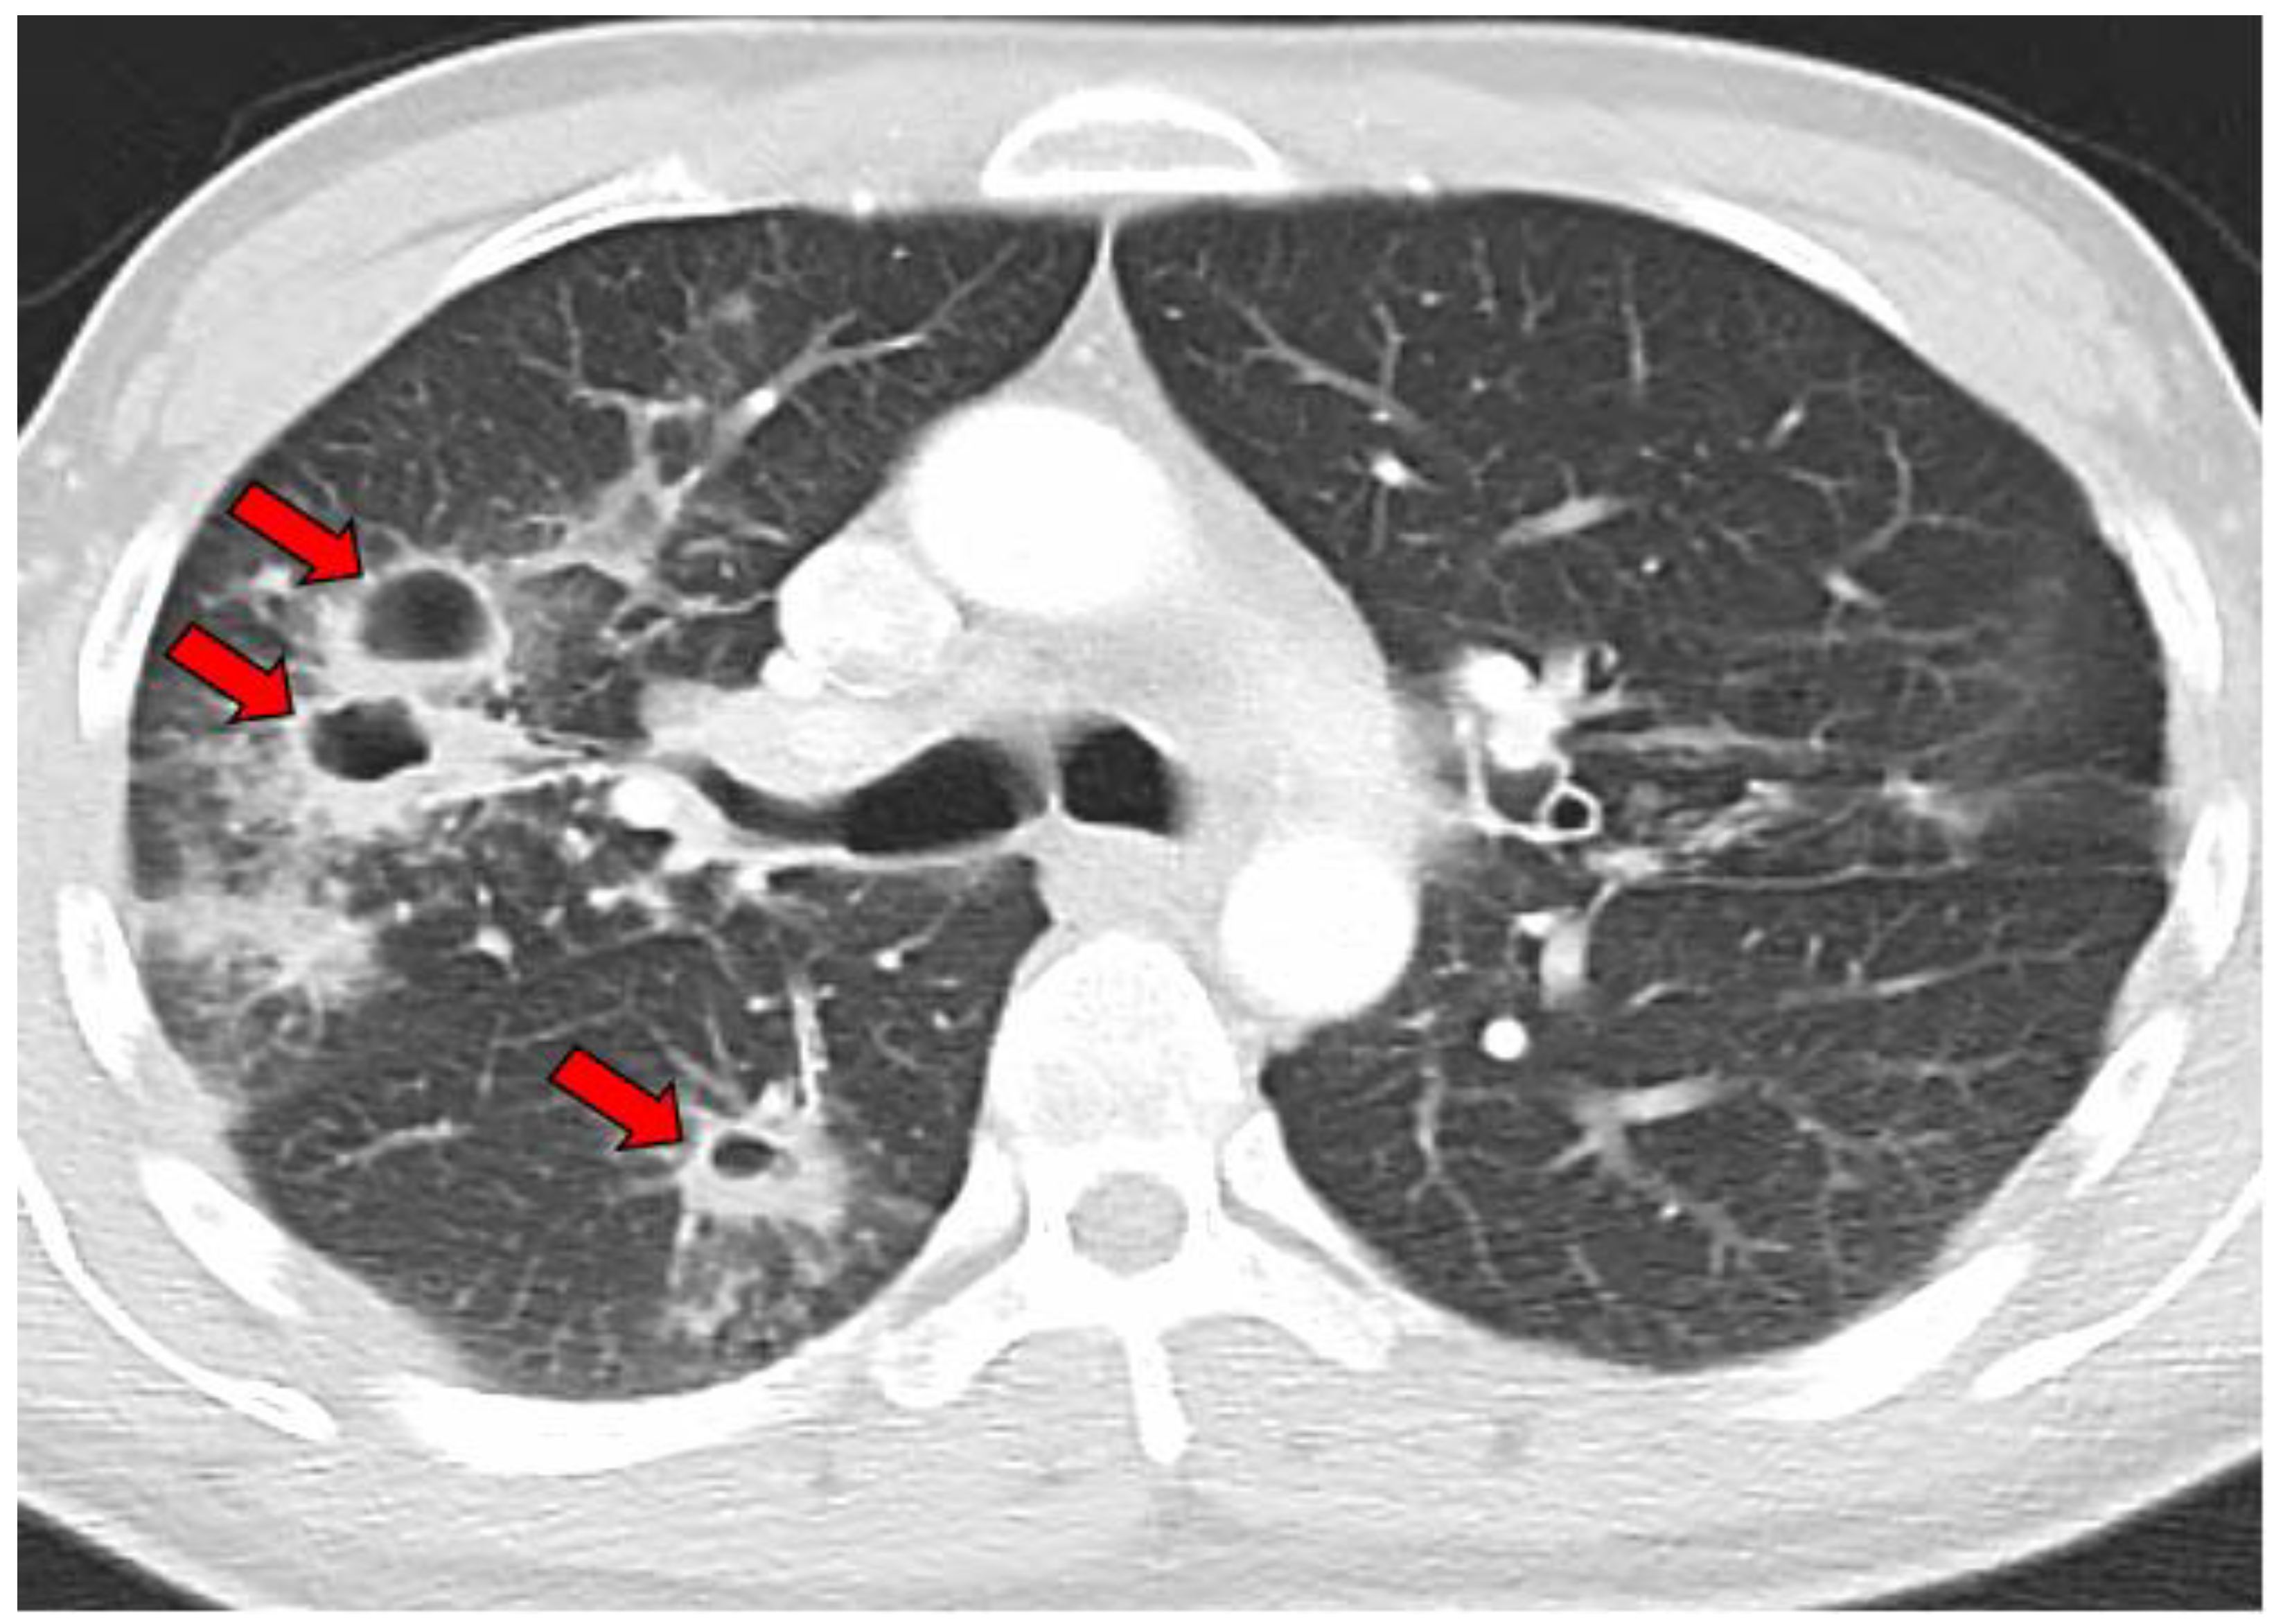

- Radiographic evidence of cavitary lesion(s) with or without concurrent infiltrative disease;

- Simple cavity and location *;

- Multiple cavities and locations *;